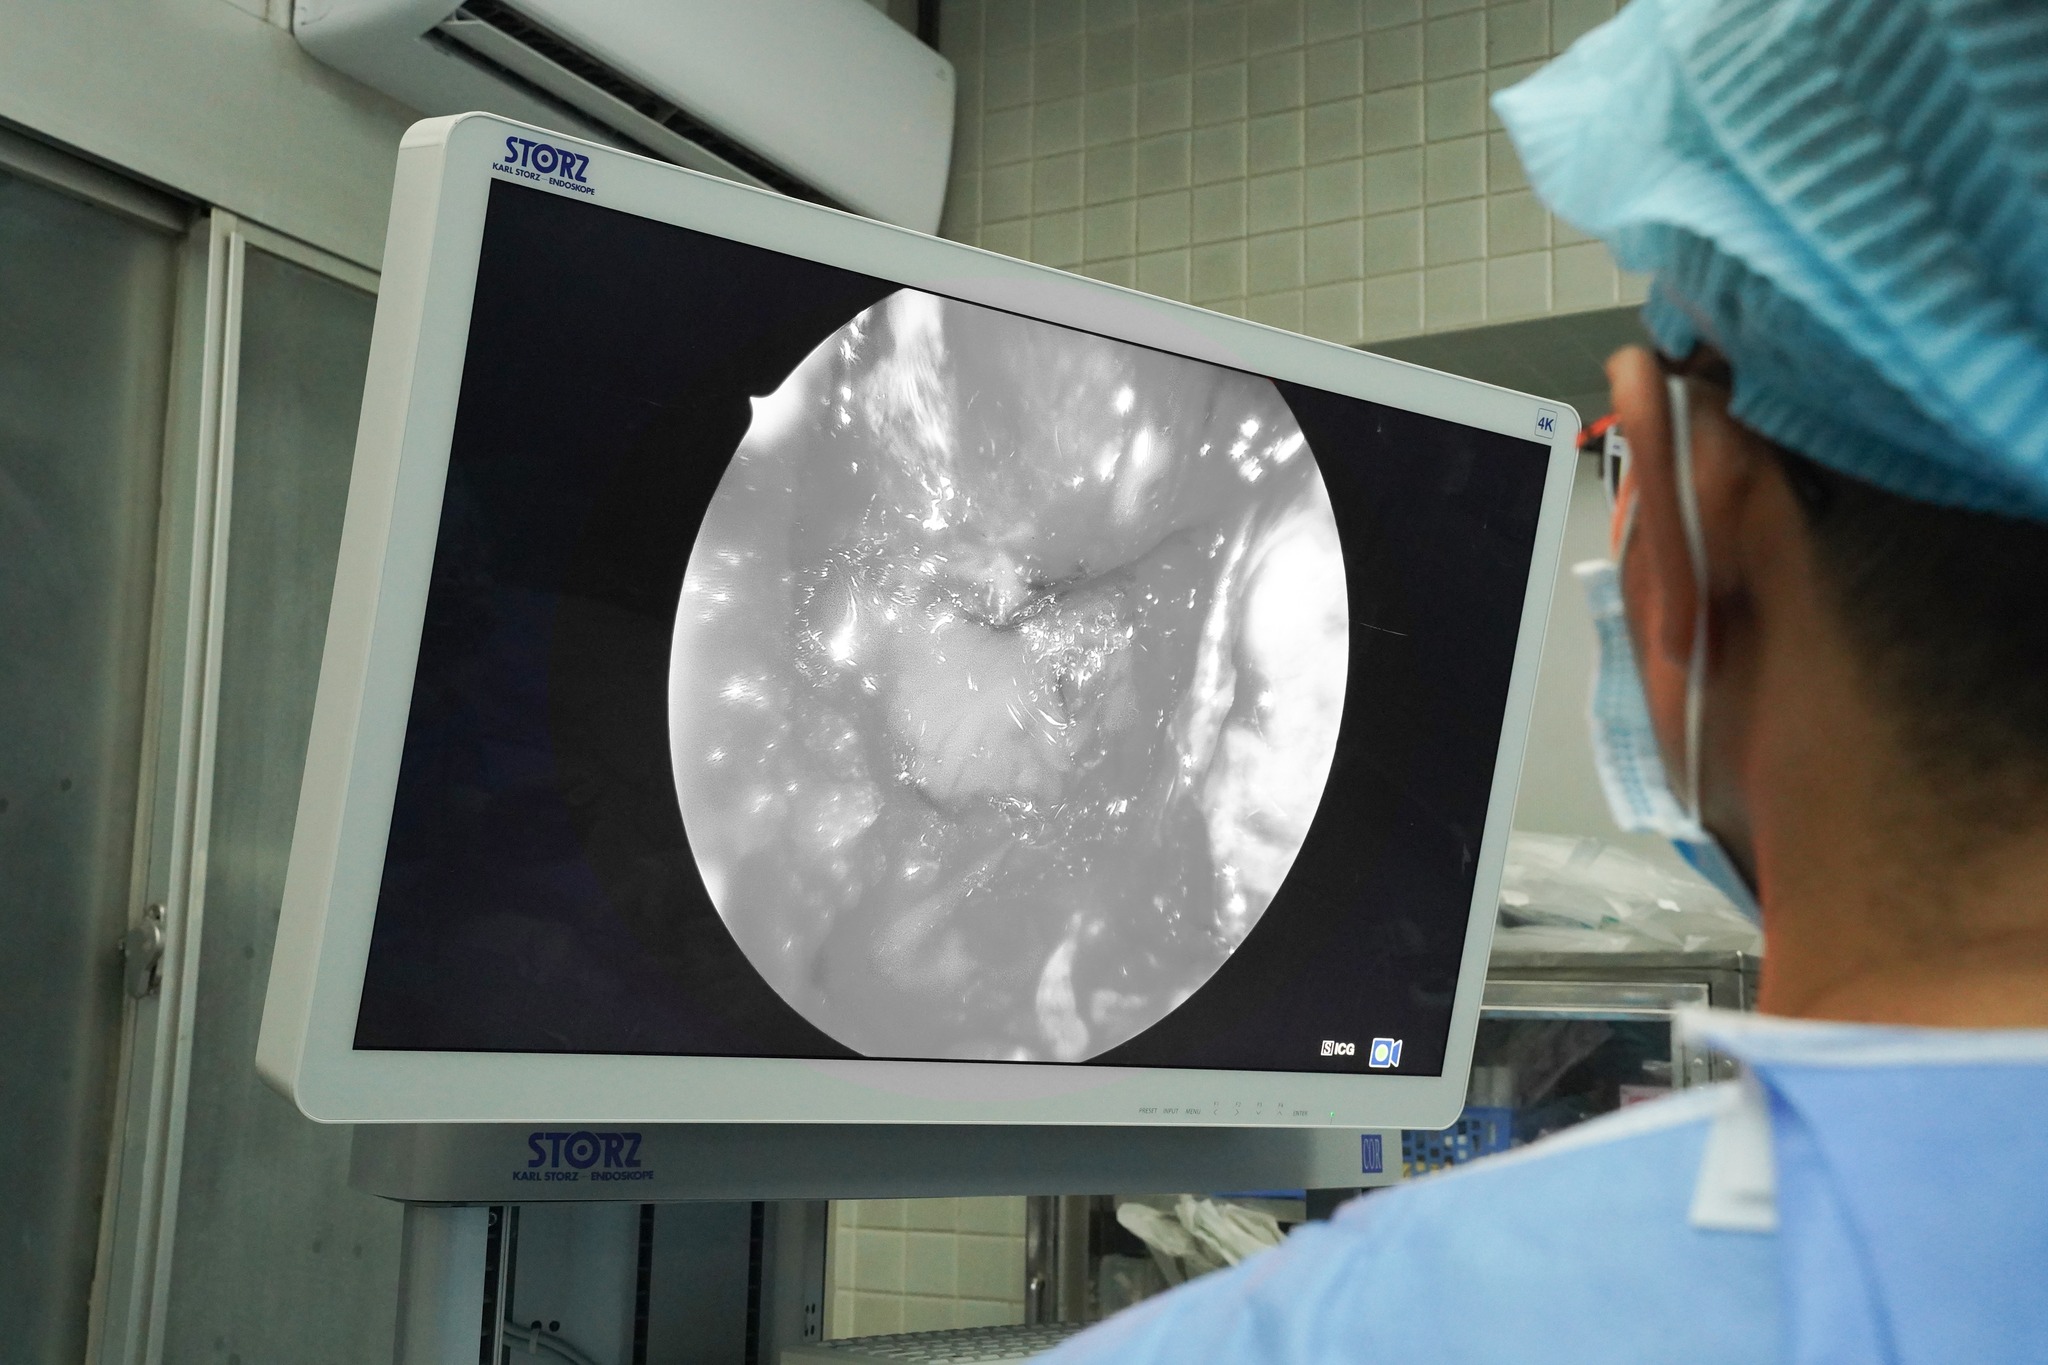

Trước tình trạng đó, ê-kíp điều trị đã quyết định thực hiện phẫu thuật nội soi qua đường mũi – xoang bướm, vốn là kỹ thuật thường quy tại khoa Ngoại thần kinh bệnh viện Chợ Rẫy. Tuy nhiên, điểm đặc biệt trong trường hợp này là ê-kíp đã sử dụng Hệ thống phẫu thuật nội soi Thần kinh 4K – ICG, 1 công nghệ hiện đại được bệnh viện Chợ Rẫy – cơ sở y tế đầu tiên tại Việt Nam, đưa vào ứng dụng từ giữa năm 2025. Hệ thống nội soi được trang bị các chức năng chuyên biệt cho phẫu thuật ngoại thần kinh, với thiết kế ống soi nhỏ gọn, chiều dài rút ngắn, chủ yếu sử dụng ống cứng và góc nhìn của scope đa dạng: 0 độ; 30 độ….

Phân tích về các ưu điểm khi áp dụng hệ thống phẫu thuật nội soi Thần kinh 4K – ICG trong điều trị các bệnh lý, TS BS Trần Thiện Khiêm – khoa Ngoại thần kinh bệnh viện Chợ Rẫy – là bác sĩ trực tiếp phẫu thuật cho bệnh nhân, cho biết: “Với trường hợp u khổng lồ như bệnh nhân này, yêu cầu quan trọng nhất là lấy được tối đa khối u nhưng vẫn bảo tồn cuống tuyến yên, tuyến yên lành và hệ thống mạch máu – thần kinh lân cận, đặc biệt là hai động mạch cảnh trong. Với hệ thống mới, khi tiêm thuốc huỳnh quang ICG, mạch máu và các cấu trúc quan trọng sẽ hiện rõ trên màn hình 4K, giúp phẫu thuật viên thuận lợi hơn trong từng thao tác. Nhờ vậy, ê-kíp đã lấy được gần như toàn bộ khối u, gia tăng hiệu quả của phẫu thuật, từ đó nâng cao chất lượng điều trị cho bệnh nhân.

Nói về sự phức tạp trong việc điều trị các dạng bệnh lý này, TS BS Trần Huy Hoàn Bảo – Trưởng khoa Ngoại thần kinh, bệnh viện Chợ Rẫy nhấn mạnh, u tuyến yên khổng lồ và các bệnh lý u sàn sọ phức tạp luôn là thách thức lớn trong chuyên ngành phẫu thuật thần kinh. Các khối u thường xâm lấn sâu, liên quan chặt chẽ đến nhiều cấu trúc mạch máu – thần kinh quan trọng như giao thoa thị giác, xoang hang và động mạch cảnh trong. Với các phương tiện trước đây, việc vừa lấy được tối đa khối u, vừa bảo tồn các cấu trúc này đòi hỏi kỹ thuật cao và tiềm ẩn không ít nguy cơ biến chứng. Chính vì vậy, khi đưa vào sử dụng Hệ thống phẫu thuật nội soi Thần kinh 4K – ICG, khả năng quan sát trong phẫu trường đã có những thay đổi rõ rệt. Phẫu thuật viên có thể phân biệt ranh giới mô u – mô lành, cuống tuyến yên và mạch máu một cách sắc nét và khách quan hơn. “Từ khi chính thức đưa vào hoạt động, Khoa đã áp dụng Hệ thống phẫu thuật nội soi Thần kinh 4K – ICG và điều trị thành công cho hơn 30 ca bệnh phức tạp về u tuyến yên khổng lồ, u sọ hầu, u màng não vùng sàn sọ, u sụn xương vùng dốc nền … giúp tăng tính an toàn và hiệu quả của phẫu thuật từ đó nâng cao chất lượng điều trị cho bệnh nhân và kết quả phục hồi sau phẫu thuật của người bệnh được cải thiện rõ rệt.